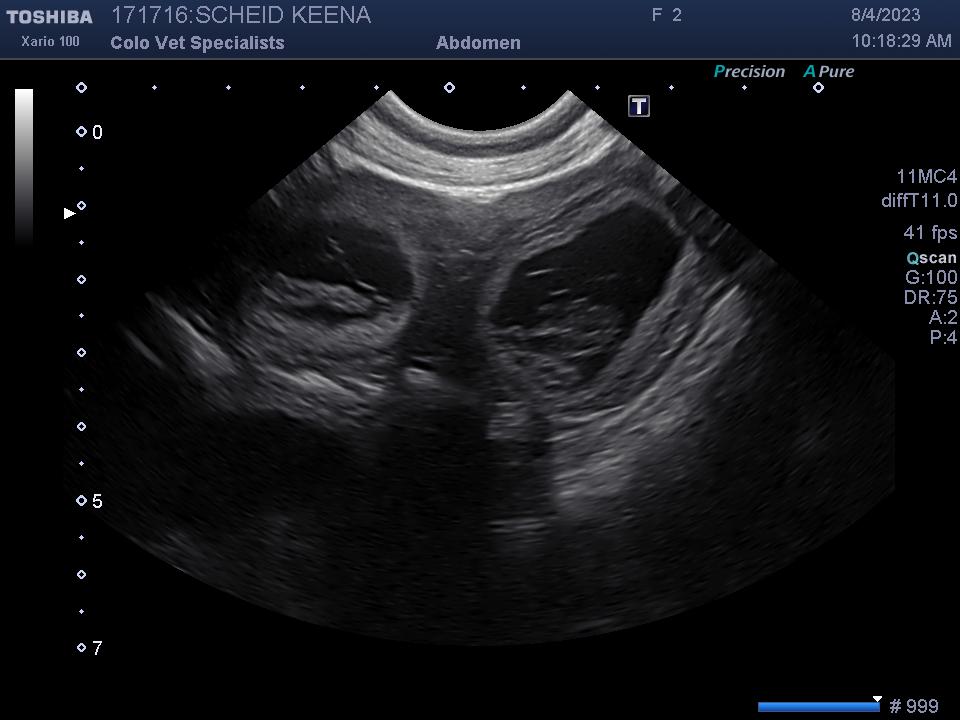

It’s official and we couldn’t be more thrilled! Keena had her ultrasound today and she is expecting a full litter. Her due date is the beginning of September and she is doing great!